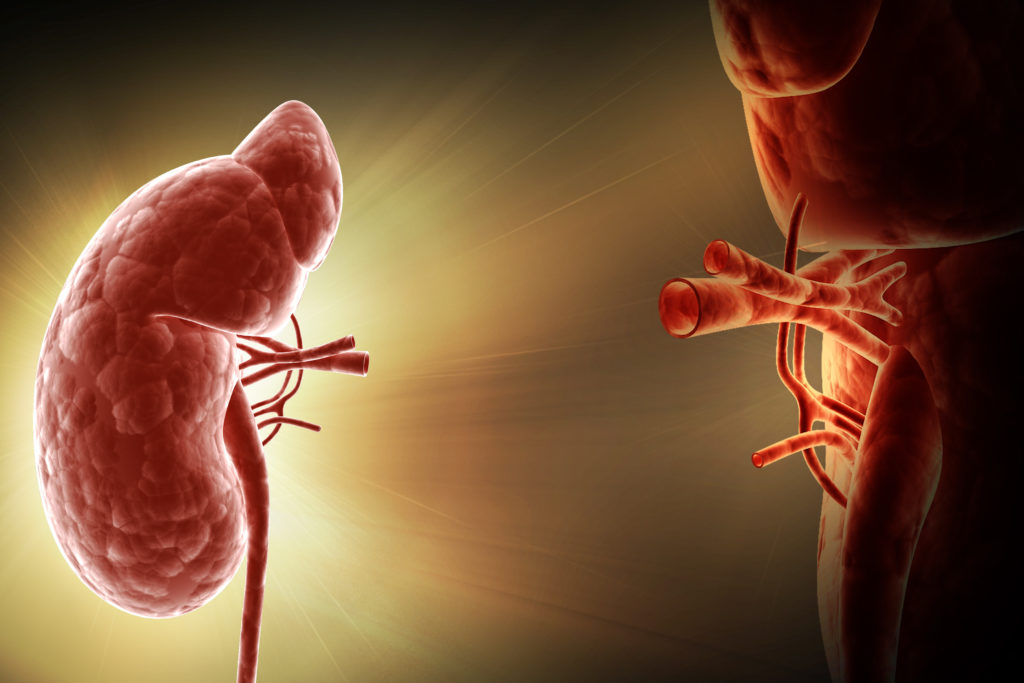

Nephrology mainly concerns with the diagnosis and treatment of kidney diseases, which includes electrolyte disturbances and hypertension, and the care of those requiring renal replacement therapy, including dialysis and renal transplant patients.